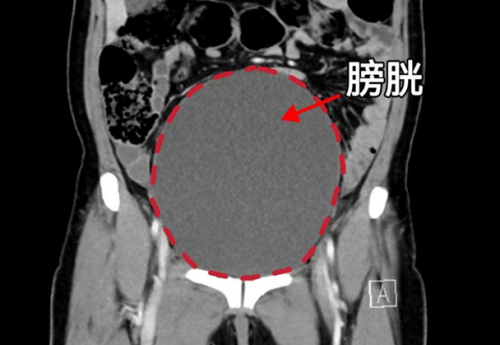

CT显示膀胱高度膨胀、尿道梗阻

91岁的刘爱华(化名)老人多年前就查出子宫脱垂,一直拖着没做手术。近日,老人因严重尿潴留、泌尿系感染,意识模糊,被家人紧急送至维多利亚老品牌76696vic(南华大学附属长沙中心医院)。检查发现,其子宫脱垂已导致尿道完全梗阻,膀胱高度膨胀,且脱垂组织因长期摩擦导致严重溃烂、感染,病情危急。

“患者20余年前就因咳嗽后溢尿就医,诊断出子宫脱垂,因为担心手术风险一直没有接受治疗,半个月之前老人出现尿频、尿痛、排尿困难,忍着没和家里人说,直到6月4日,发现有肿块从阴道口脱出,内裤上有血迹才被家人送医。”据维多利亚老品牌76696vic妇产科三区主任魏馨介绍,经检查发现患者为子宫脱垂三度(Ⅳ期),子宫和阴道前后壁完全脱出阴道口,由于脱出的组织压迫尿道,造成尿道梗阻、尿潴留、泌尿系感染,同时还合并有支气管扩张并感染、低蛋白血症、轻度贫血等情况。